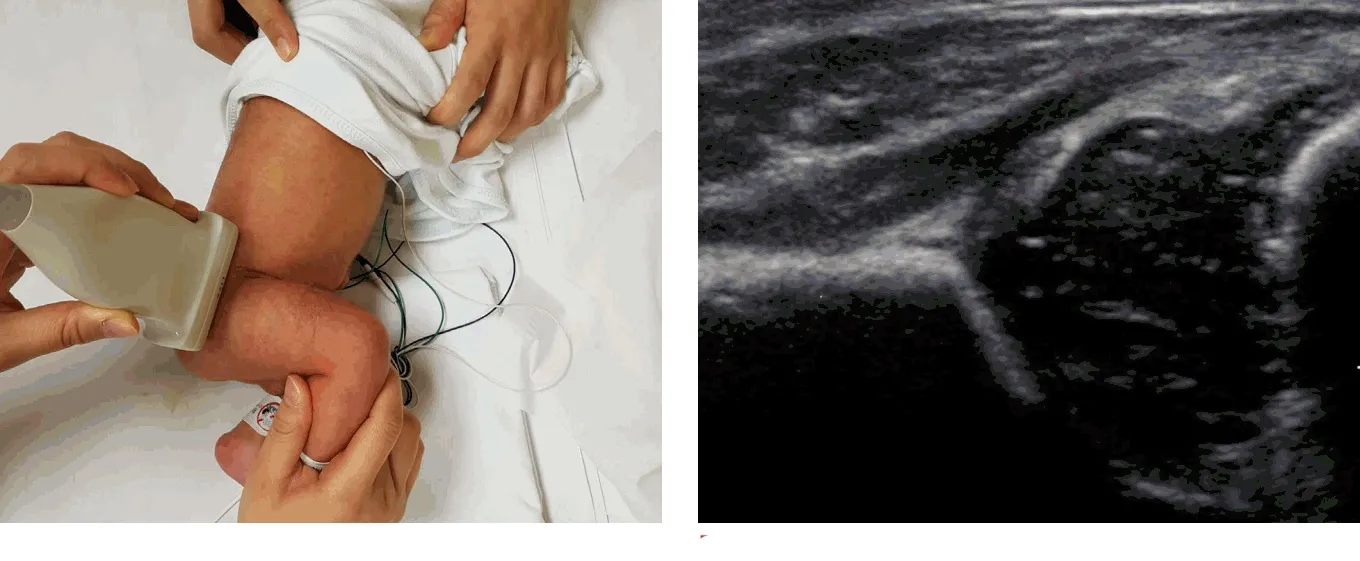

Как проводится исследование?

УЗИ тазобедренного сустава от Прайв обычно проводится в положении пациента лежа на спине или на боку. Врач наносит специальный гель на область сустава, чтобы улучшить контакт датчика с кожей и обеспечить лучшее качество изображения. Затем датчик перемещается по коже, передавая ультразвуковые волны, которые отражаются от тканей и создают изображение на экране.

Что можно увидеть на УЗИ?

УЗИ позволяет визуализировать:

- Костные структуры тазобедренного сустава.

- Хрящевую ткань.

- Синовиальную оболочку.

- Мягкие ткани, включая мышцы и связки.

- Наличие жидкости в суставной полости (например, при воспалении).